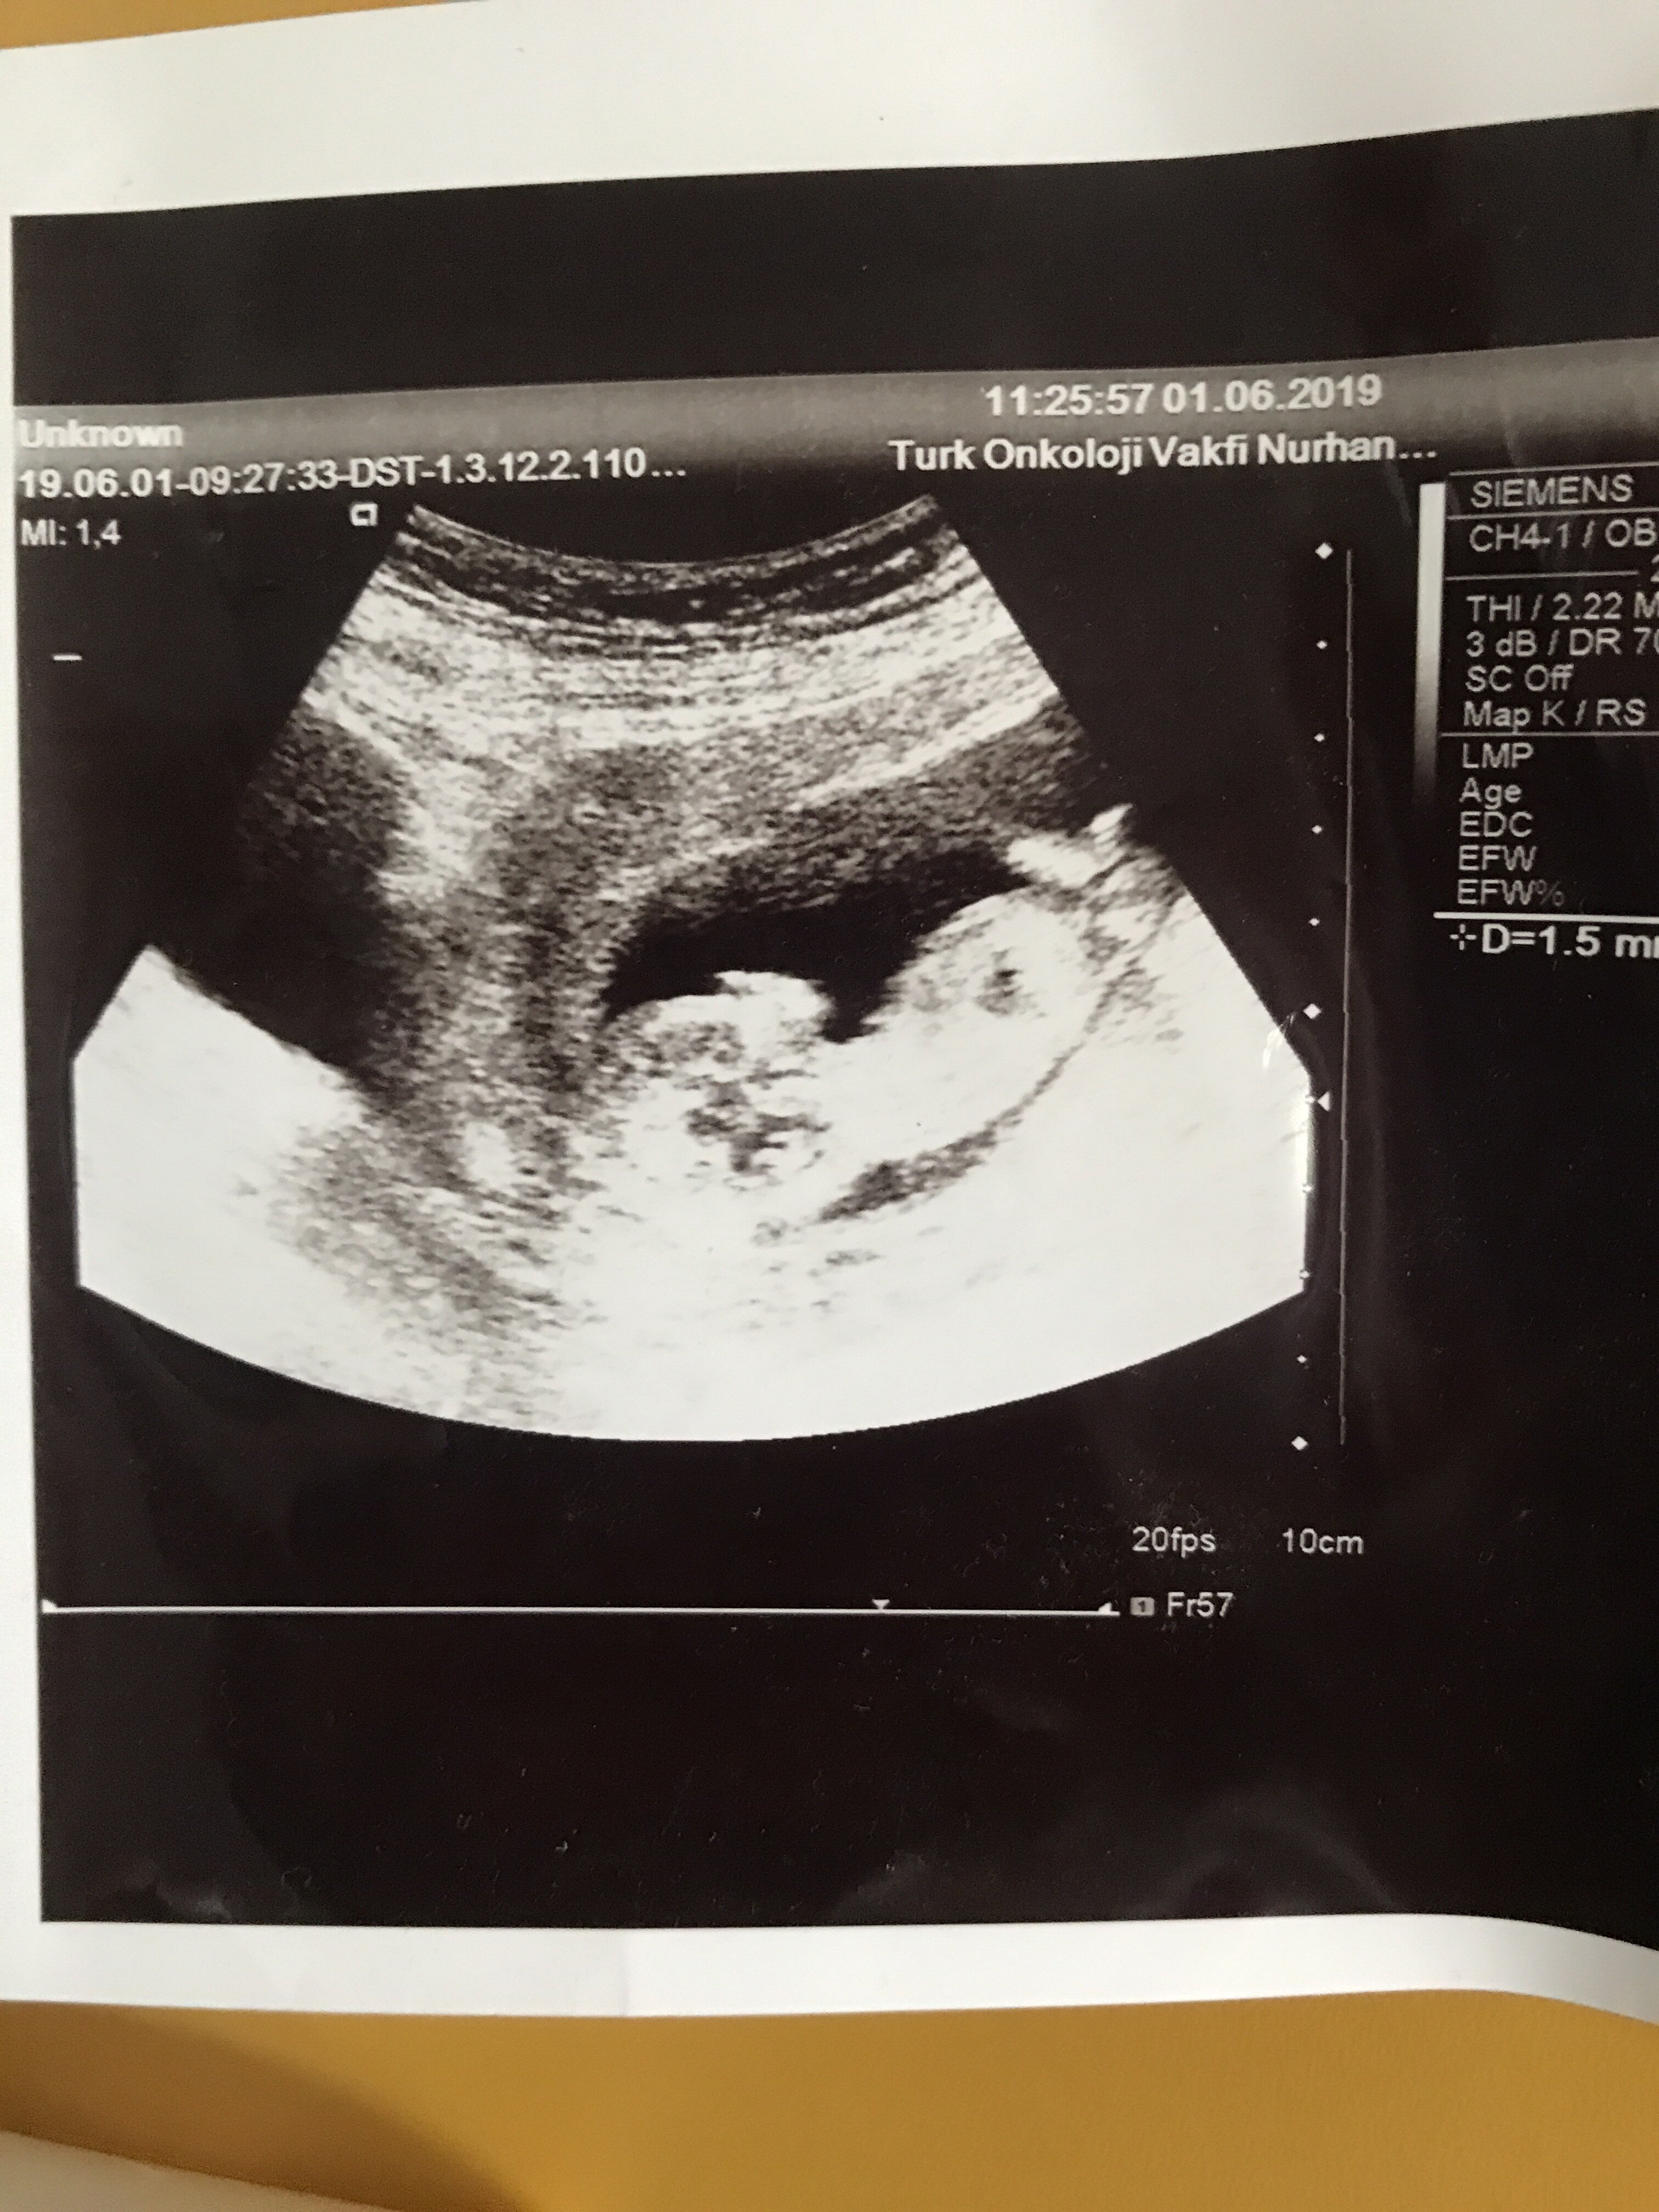

Tam net değil ama iyice yakınlaştırınca bebeğin cinsiyeti erkeğe benziyor. Tabi bebeğin cinsiyetini 20 . haftalarda net öğreneceğinizi de belirtelim.Sağlıklı gebelik geçirmeniz dileği ile.

Çok teşekkür ederim vakit ayırıp cevap verdiğiniz içinSelamlar sevgili dilara inceledim baştan aşağıya yüzde yüz kız gibi görünüyor hayırlı olsun